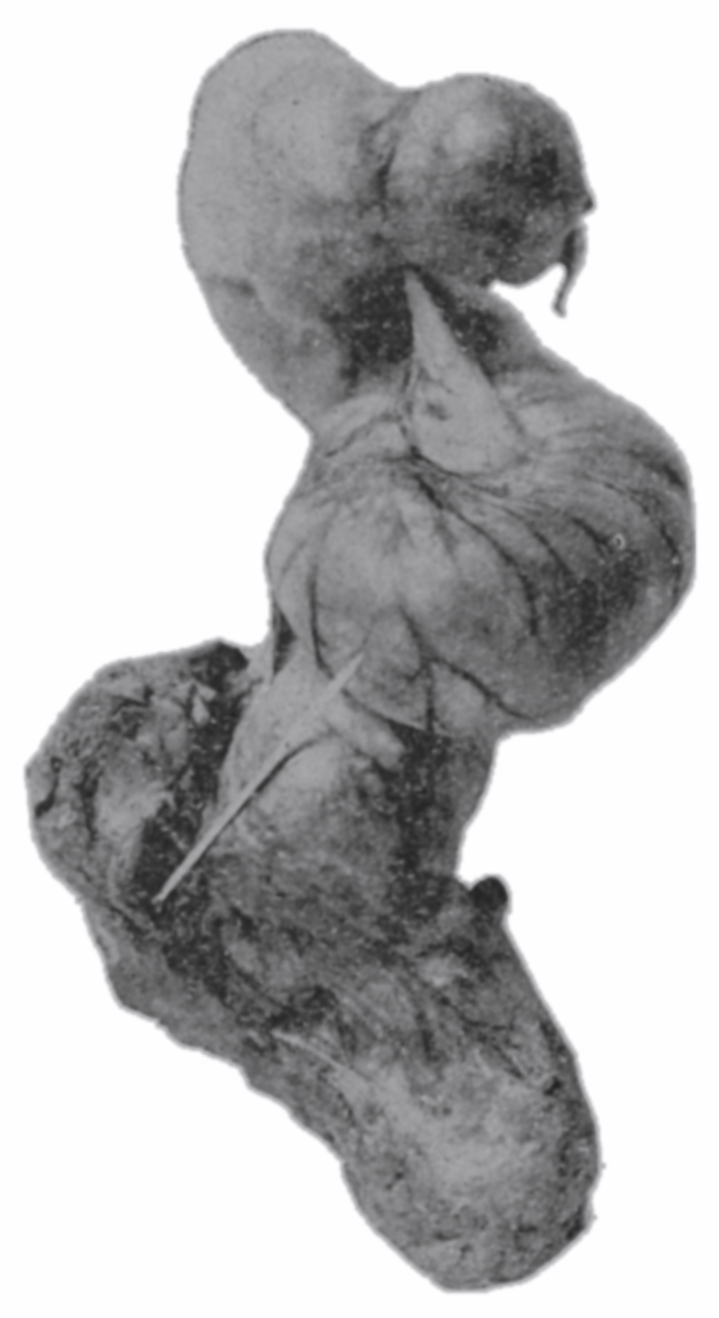

Fig. 19.—Drawing of specimen No. 281 in the Anatomical Museum of the Royal College of Surgeons, London. The dissection was made by Mr. William Pearson. The drawing shows in the lower part of the field the coccyx, in the upper part of the field the pubes.

The fixed anal rectum begins at the levator ani and coccygeus muscles. The levator ani has its origin at the sides of the bodies of the pubic bones, the coccygeus at the spines of the ischii, and the levator ani has additional origin from the fascia and bony parts on a line between these two points. The fibers of these muscles are directed downward and inward to the fixed anal rectum; many fibers are blended into the contiguous structures of the pelvic floor. The coccygeolevator muscles may be compared to an opened slat-fan, the apex having its place at the anus, and its long border representing the line of origin of the muscles, Fig. 19. The ental sphincter ani muscle, situated a few lines below the levator ani, is made up of an aggregation of the fibers of the circular non-striated muscular intestinal coat, Fig. 20. The ectal sphincter ani striated muscle is situated immediately beneath the external skin. It serves the present occasion to describe the ectal sphincter of the male as a loop of muscle thrown about the terminal end of the rectum and hitched to the terminal bone of the coccyx, and in the female as a longer loop of muscle twisted upon itself so as to make a tandem-loop,[56] which, in the form of the figure eight (8), is thrown about the vagina and terminal end of the rectum.